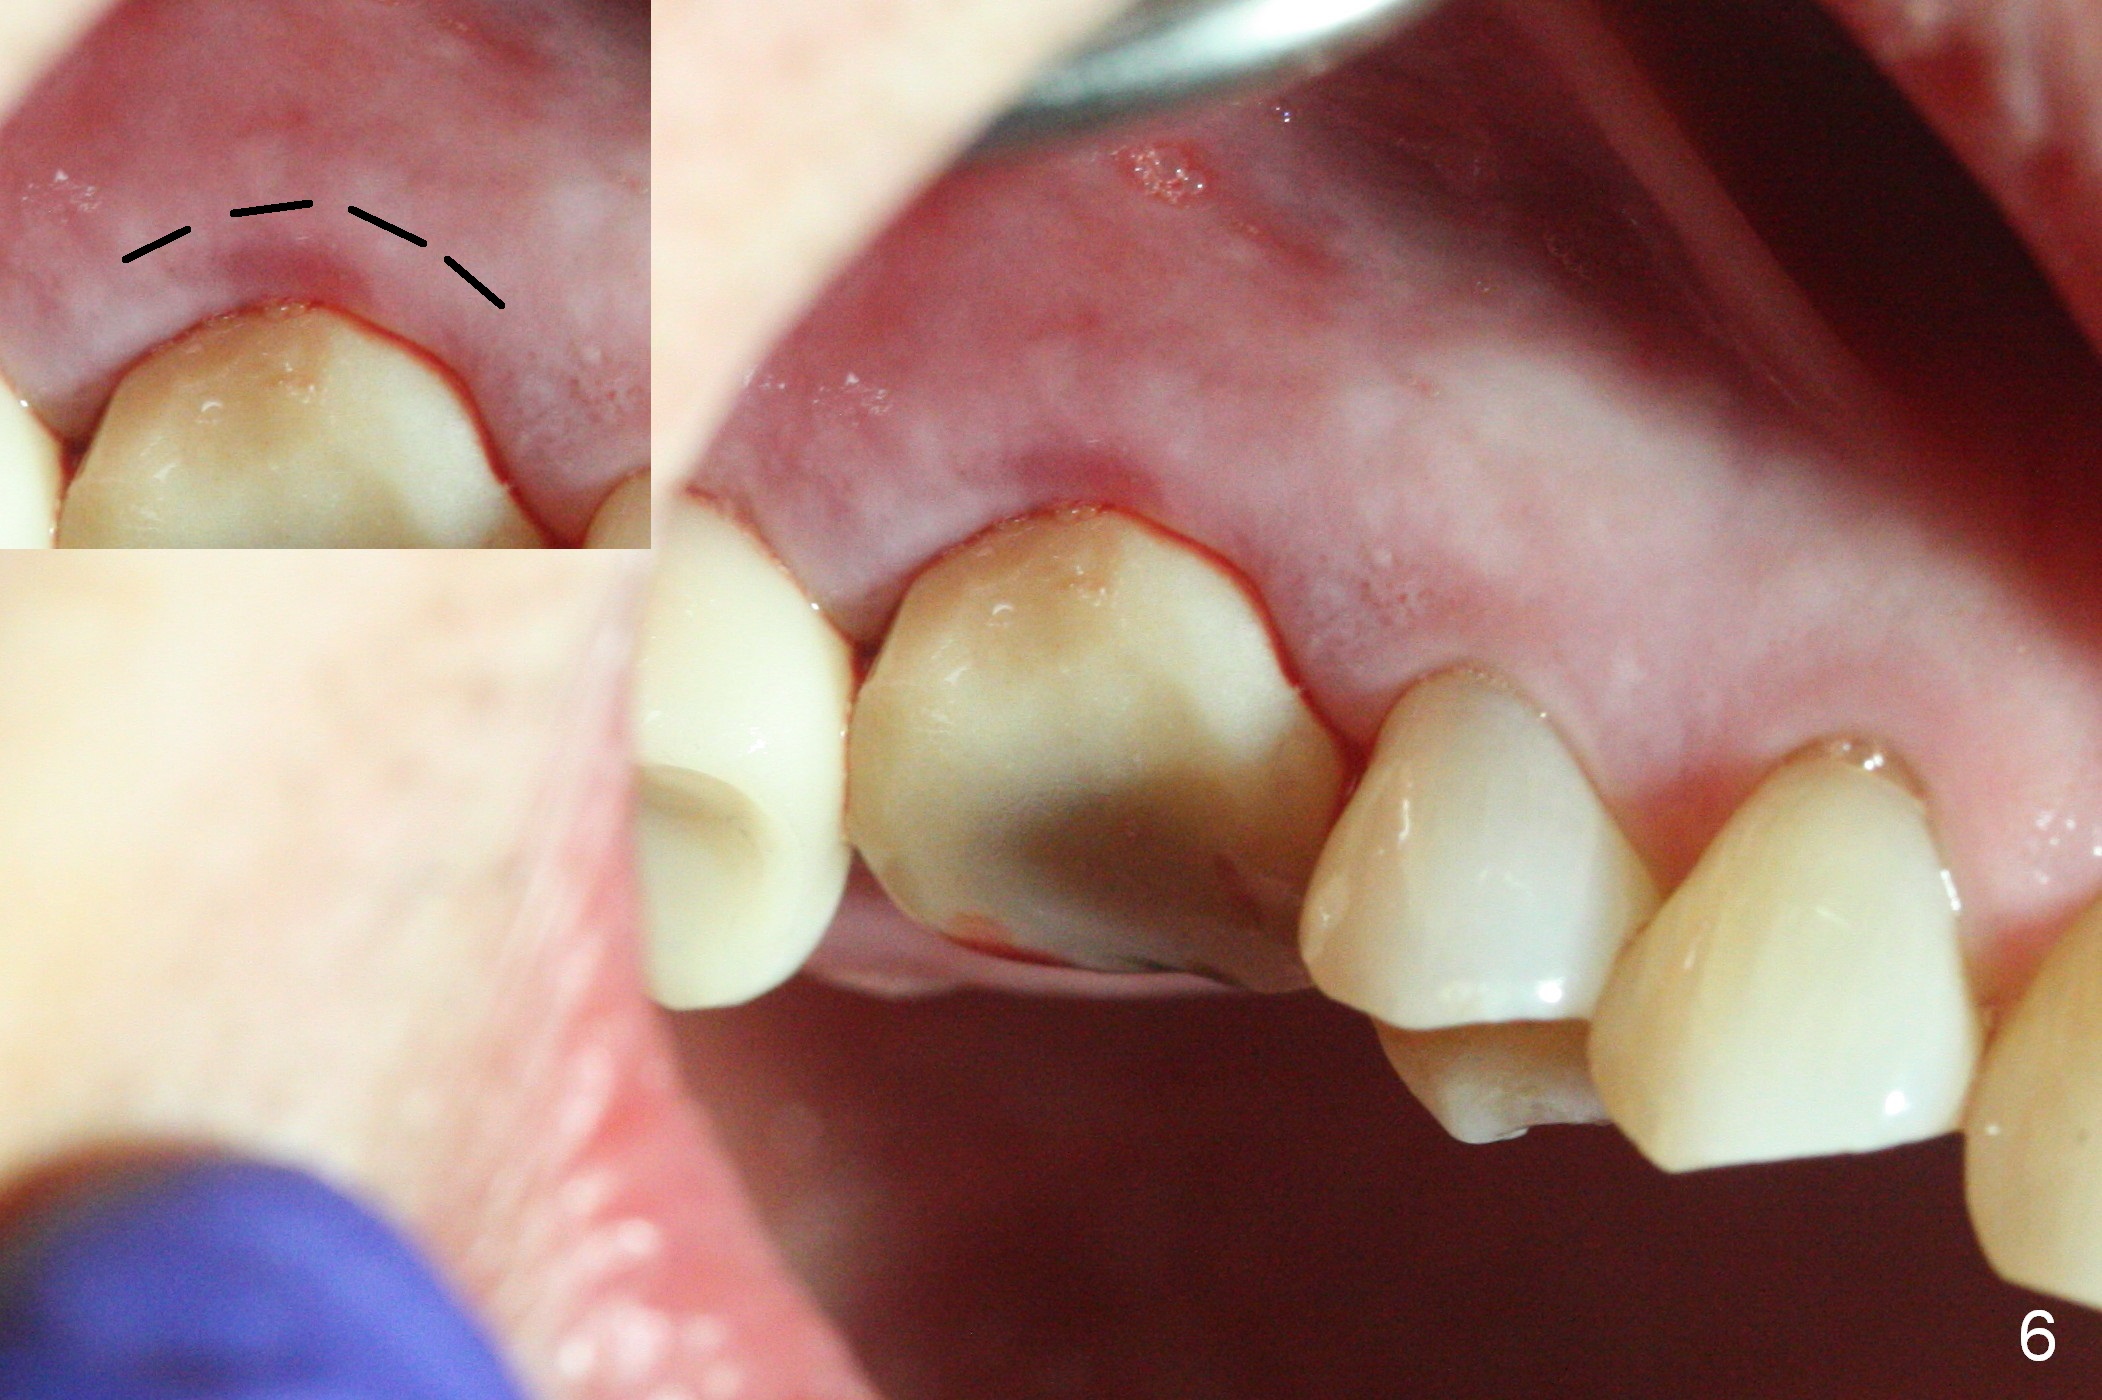

Heavy bruxism is characterized by the crack at #3 (symptomatic, requiring emergency extraction) and loss of the palatal cusp at #5 (Fig.1). Osteotomy is initiated in the septal slope (Fig.2 S) with a 1.6 mm pilot drill for 9 mm (with sudden empty feeling), followed by Marking bur. After 4.3 mm Magic Drill is used for ~ 9 mm, the sinus membrane is found to perforate. A dummy implant (5x9 mm, 2 mm shorter than design) is placed short of the sinus floor (Fig.3 ^). Prior to placement of 5.5x9 mm IBS implant (~ 35 Ncm, Fig.4,5), a piece of Osteogen plug is inserted into the osteotomy for repair of the perforation. The final implant is also shy of the sinus floor (Fig.5 ^). The Osteogen plug is apparently placed underneath the sinus floor so that it should be able to repair hard and soft tissue defects. The remaining sockets are mainly filled with Osteogen plug, while the implant plateau is covered by autogenous bone and Osteogen. When a 6.5x4(3) mm abutment is placed, an immediate provisional is fabricated (Fig.6) with its margin placed subgingival (Fig.6 inset dashed line). This innovative design of the provisional is to prevent collapse of the most coronal gingiva and loss of bone graft, particularly where the bony plate is defective. Although there is mild pain postop, nasal hemorrhage or discharge is absent.